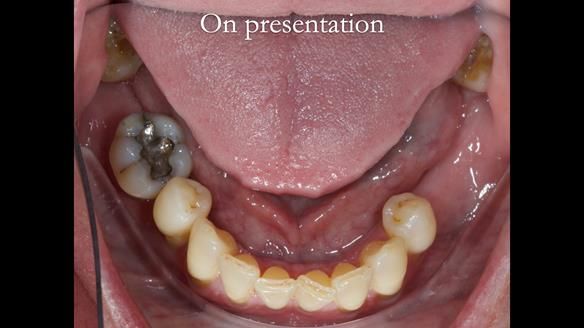

Welcome to my Newsletter 58, where I show the making and fitting of an upper gasket partial denture for Zoe (52 year old woman). This issue provides a comprehensive overview of the entire protocol workflow for this superbly retained denture.

Zoe was referred to me for specialist prosthodontics by her general dentist, after unsuccessful attempts to provide a denture because of fractures, looseness and discomfort.

Diagnoses

The current denture could be enhanced both in terms of fit and aesthetics.

The upper left first molar demonstrated excellent condition, with no signs of mobility, caries, or periodontal issues.

The remaining natural teeth were invaluable. I advised continuing regular appointments with her General Dentist to ensure the preservation of these natural teeth for as long as possible. I emphasised it is crucial to maintain the remaining natural teeth with meticulous daily cleaning, especially where they emerge from the gums.